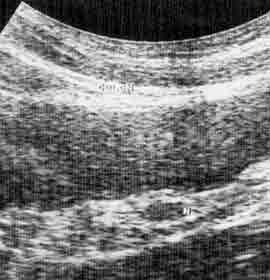

Ультразвуковое исследование брыжейки толстой кишки.

Рис. 2. Туберкулезный мезаденит сигмовидной кишки. (Слева) Ультразвуковая ирригограмма. (Справа) Схема.

1 - увеличенный лимфатический узел брыжейки,

2 - просвет сигмовидной кишки,

3 - очаги пониженной эхогенности за счет воспаления брыжейки,

4 - брыжеечный край сигмовидной кишки,

5 - край брыжейки сигмовидной кишки.